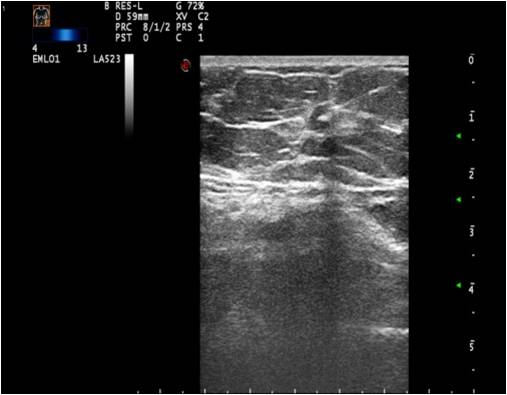

Ultrasonography can help in their differentiation; can depict anechoic cystic lesions (Picture17.) or solid masses (Picture 18.). These lesions usually each have a smooth, sharp edge and echo-enhancement can appear behind them. Rarely, cysts contain tumors. (Picture19.).

Ill-defined margins, with uneven contours and blurred edges are usually characteristic of malignant lesions. During ultrasound examination echo-attenuation occurs frequently behind these inhomogeneous hypo-echogenic masses (Picture 20).